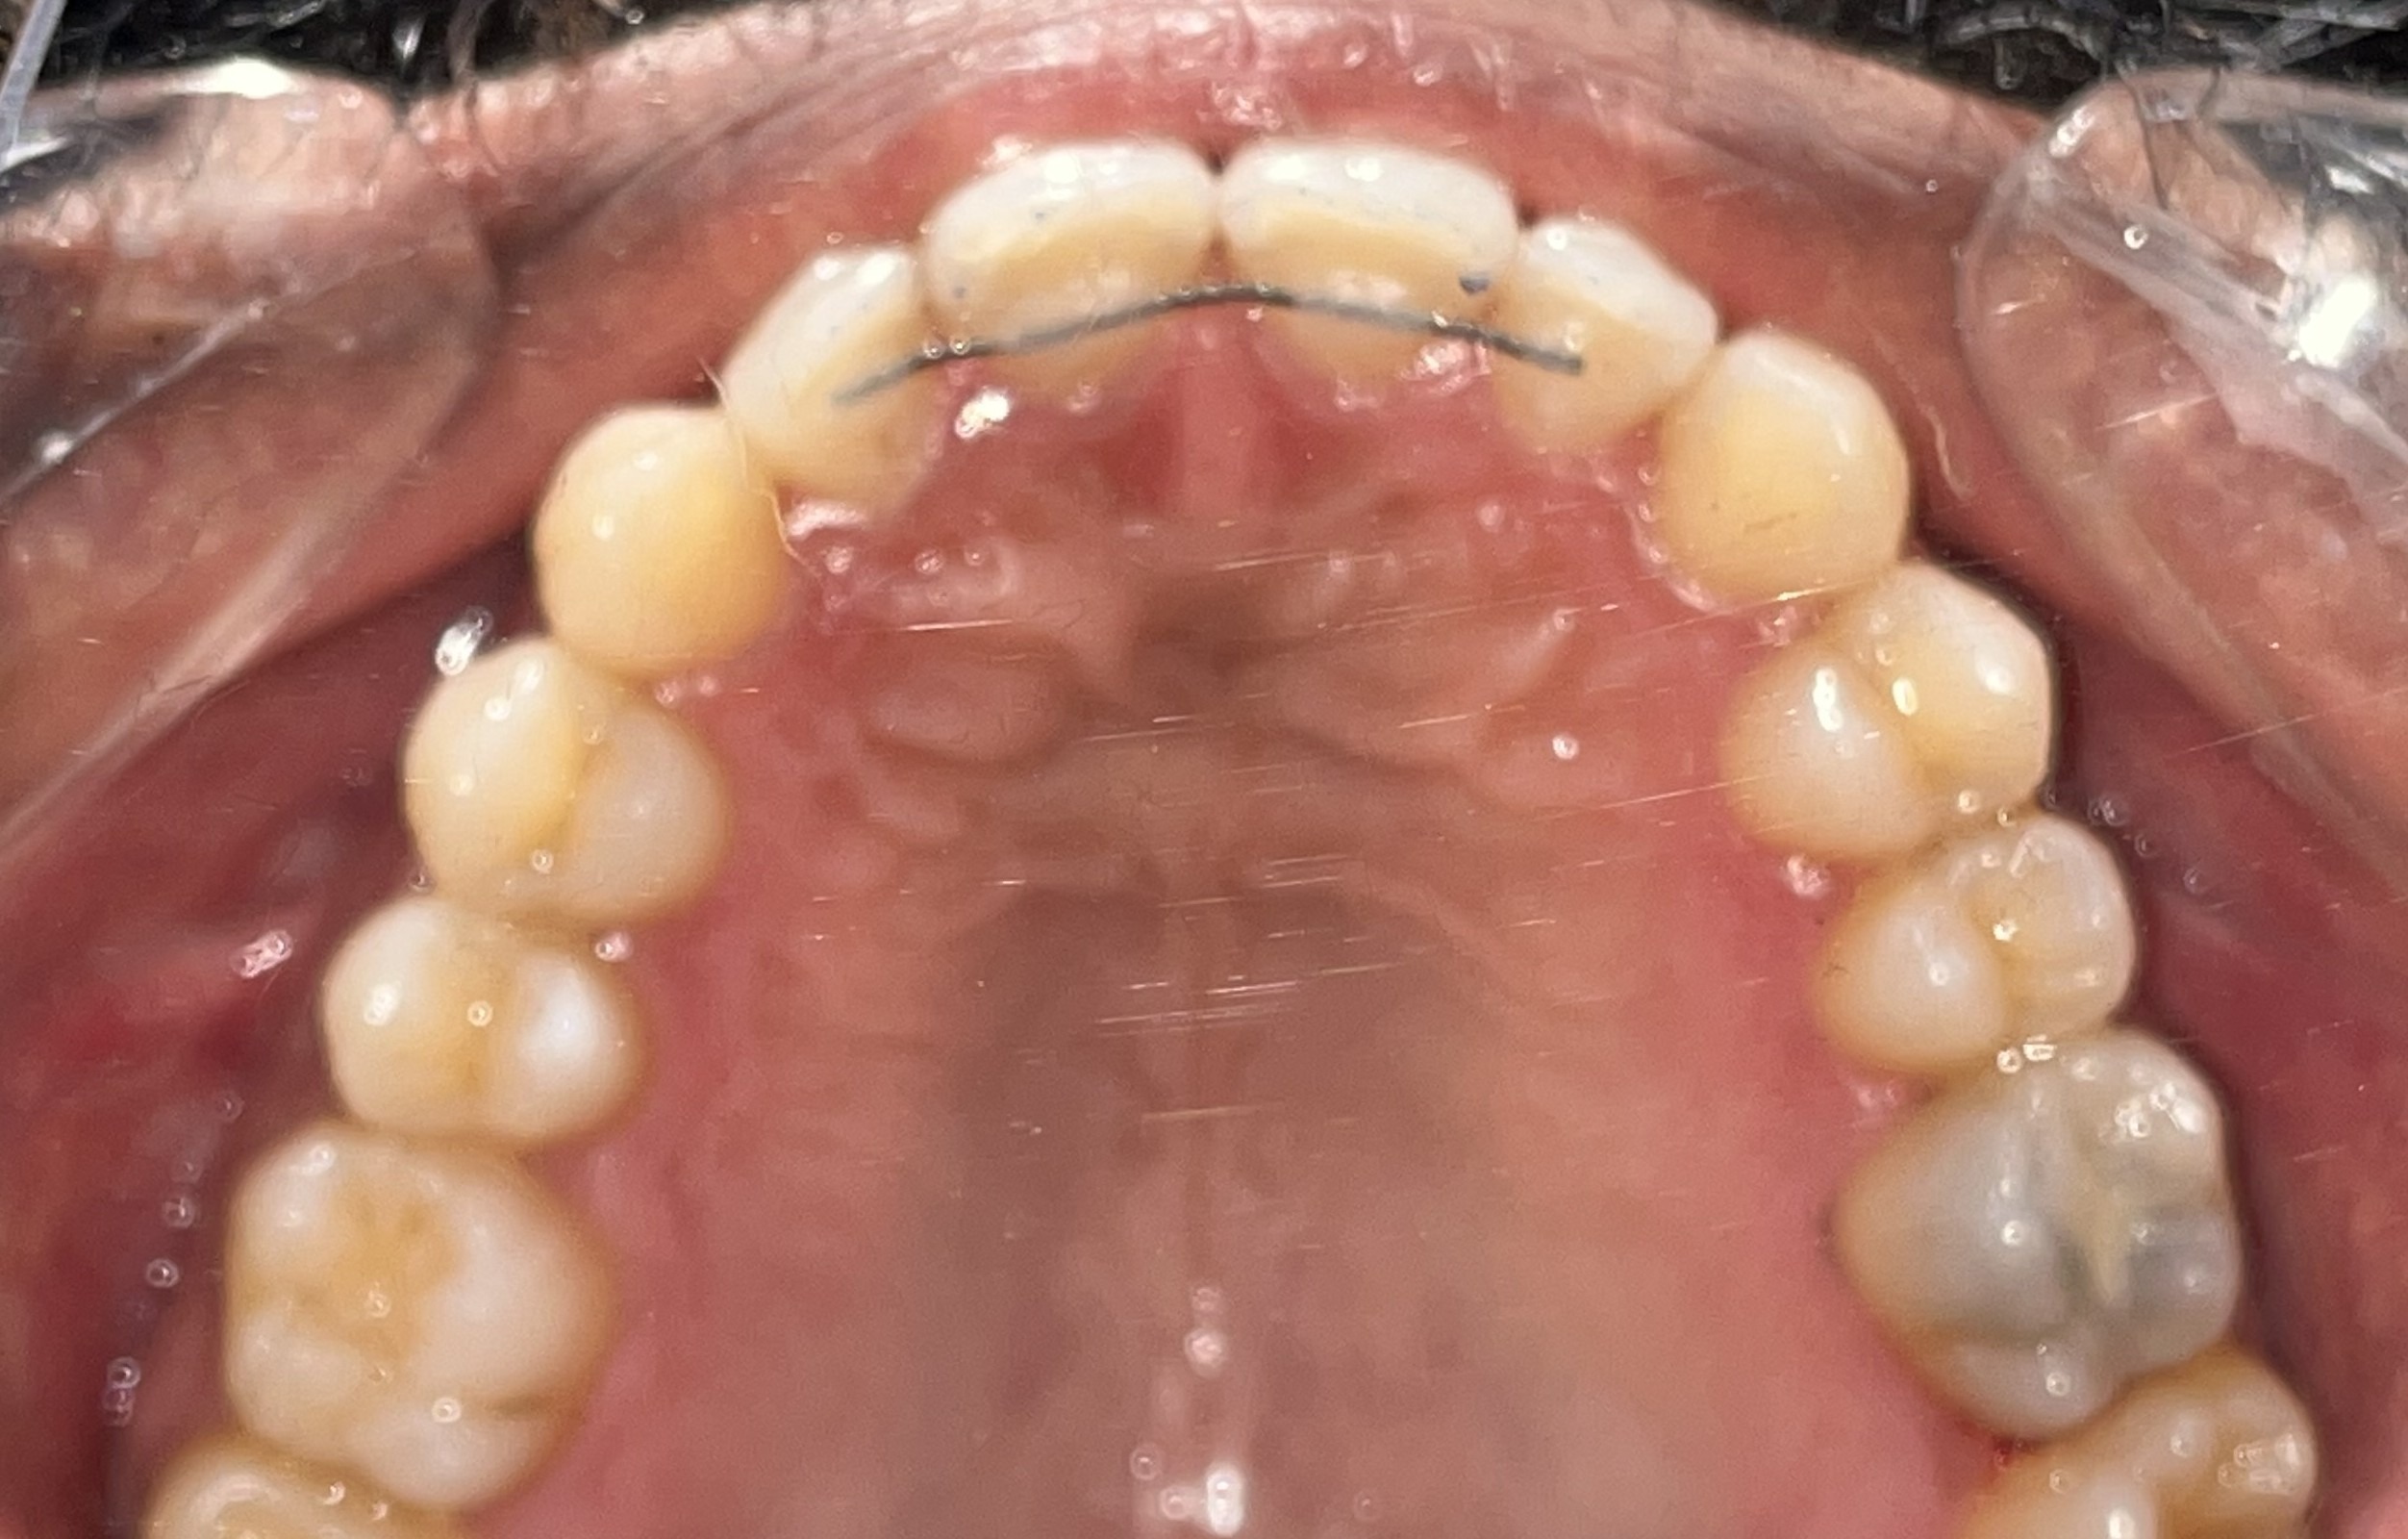

Before: Upper

During The Treatment